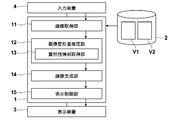

- the image acquisition unit 11 acquires the first image V1 and the second image V2 from the storage 2 to the memory.

- the image processing apparatus 1 detects that a predetermined alignment function is selected in the selection menu, the image processing apparatus 1 prompts the user to select or input information necessary for specifying the first and second images. Then, when the first and second images are specified by the user's operation of the input device 4, the image acquisition unit 11 acquires the first image V1 and the second image V2 from the storage 2 to the memory.

- the image generation unit 14 generates an image V1A obtained by converting the first image V1 using the conversion function determined by the image deformation amount estimation unit 12.

- FIG. 2 is a flowchart illustrating a processing flow of the image processing apparatus according to the second embodiment. The processing flow will be described with reference to FIG. First, the image acquisition unit 11 acquires a first image (first image data) V1 and a second image (second image data) V2 obtained by imaging a subject (S01).

- the image generation unit 14 converts and reconstructs the first image using the determined conversion function, and generates the image V1A (S08). Then, the display control unit 15 displays the generated image V1A and the second image V2 side by side so that they can be compared (S09).

- FIG. 5 is a schematic diagram showing a functional block diagram of the second embodiment.